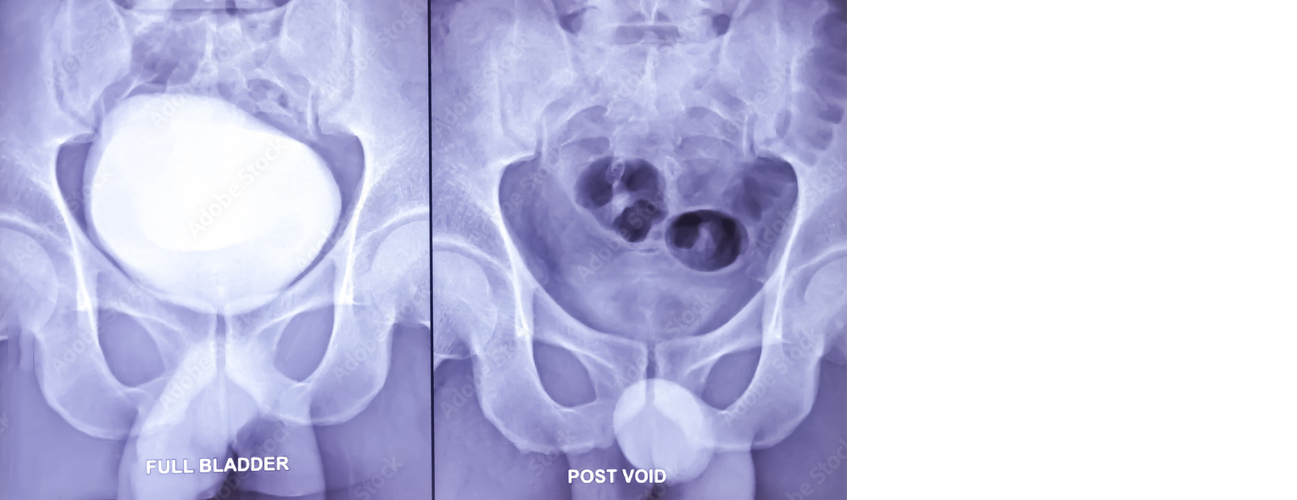

MCU (Micturating Cystourethrogram) and RGU (Retrograde Urethrogram) are diagnostic imaging procedures used to assess the structure and function of the urinary tract, specifically the urethra and bladder. These tests are particularly useful in evaluating patients with suspected urinary tract abnormalities, trauma, obstructions, or recurrent infections.

MCU (Micturating Cystourethrogram): This procedure involves taking a series of X-ray images while the patient urinates. A contrast dye is inserted into the bladder through a catheter, and as the patient voids, X-ray images capture the flow of urine from the bladder through the urethra. MCU helps detect abnormalities such as vesicoureteral reflux (where urine flows backward from the bladder into the ureters), bladder or urethral abnormalities, strictures, or obstructions. It's commonly used in children with recurrent UTIs or congenital abnormalities.